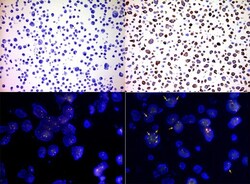

- Main image

- Experimental details

- Immunocytochemistry staining of paraffin-embedded human cell line H1975 (upper left) and H2228 (upper right) on IHC antibody quality control slide using anti-ALK mouse monoclonal antibody TA801287 (1:400). The ALK rearrangement in H2228 cells is labeled with ALK Breakapart probe in FISHtest (lower right, 60X) and the control of H1975 cell at the same FISHprobe test (lower left, 60X).